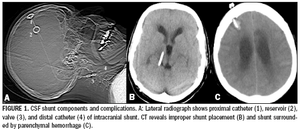

Implanted medical devices such as neurostimulators,cardiac pacemakers, cochlear implants, and infusionpumps have become common.